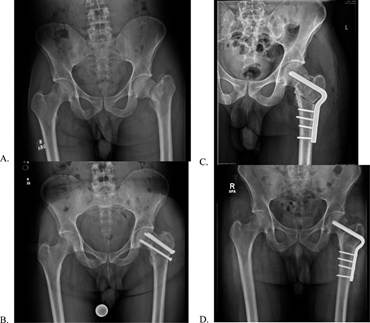

X-ray images showing a femoral neck fracture before treatment and after surgery (Bernstein,2022)